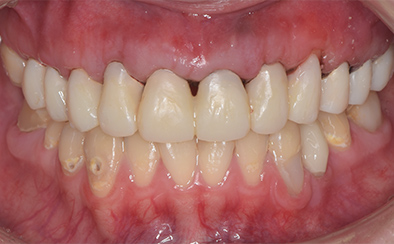

歯ぐき(歯肉)の治療も大切です。歯ぐきを健康的な状態に治療していくことで、お口全体を審美的に優れた美しい状態に改善できます。このように歯ぐき(歯肉)の治療を行うことで、炎症を抑え、健康な状態をつくることができます。歯ぐきのコンディションを回復させると同時に、仮歯を入れます。しかしこれは治療中の隙間を埋めたり見た目を取り繕う「仮歯」とは異なります。プロビジョナルレストレーションと言い、最終的な歯(本歯)と同じ形体をもつ歯で、治療した歯や周囲の歯、反対側の歯、歯ぐきなどお口全体の回復と調和を整える大切な治療プロセスです。もちろんこの期間に仮歯での噛み合わせ、咀嚼や嚥下、または発音や発語など機能的な回復に不具合がないか、顎関節への影響や負担がないか検証する期間でもあります。

仮歯で機能回復の確認を行い、そしてさらに微調整を行います。機能的・審美的に改善を確認できた仮歯の形態を元にセラミックスクラウンを作製します。熟練した歯科技工士によるセラミックス制作を行い、装着後に最終的な微調整(咬合調整)を施し、むし歯治療、歯の根の神経治療(根管治療)、白いセラミックスによる修復治療のすべてが終了しました。